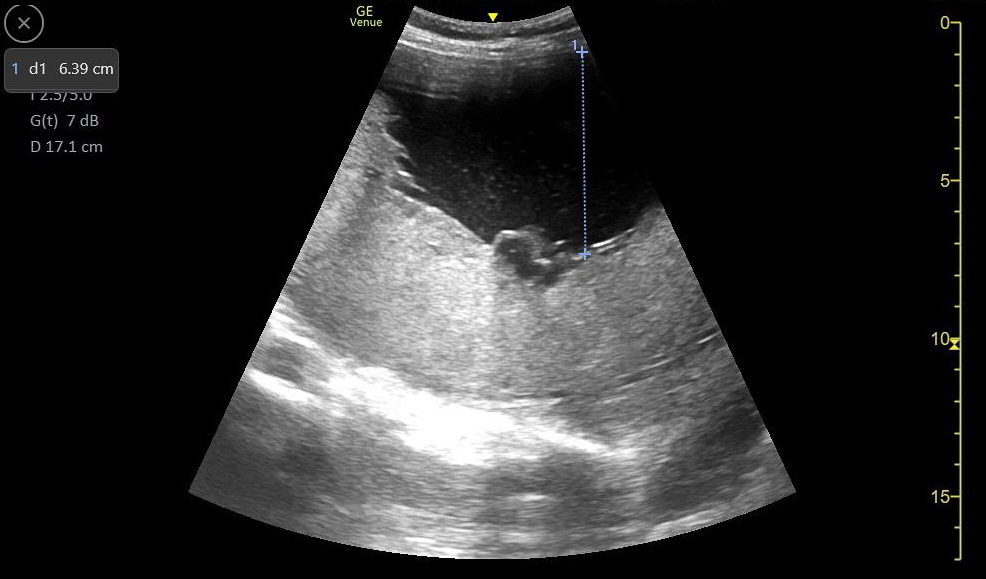

Figure 49. Mild hydronephrosis seen on long axis view of the kidney. Note the mild dilation of the renal pelvis and calyces and the lack of color Doppler flow over the anechoic (black) dilation of the renal pelvis.

Figure 50. Moderate hydronephrosis seen on long axis view of kidney without a change in the thickness of the renal cortex.

Figure 51. Severe hydronephrosis seen on long axis view of the kidney. Note the severe dilation of the renal pelvis and thinning of the renal cortex, as well as the dilated ureter extending to the right of the image.